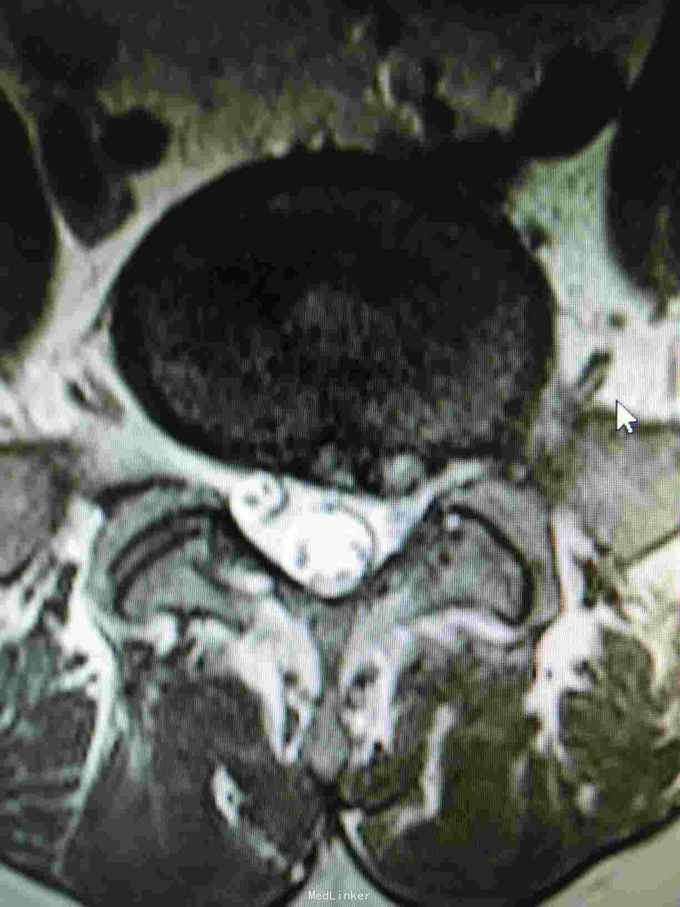

腰椎间盘突出 腰椎间盘突出症 骶管囊肿

1:腰椎间盘突出症2:骶管囊肿

该患者L4/5椎间盘中央突出,L5/S1椎间盘向左突出。手术右侧L4/5,L5/S1开窗,见骶1神经根与骶管囊肿粘连,压迫变性,水肿,变粗硬化。